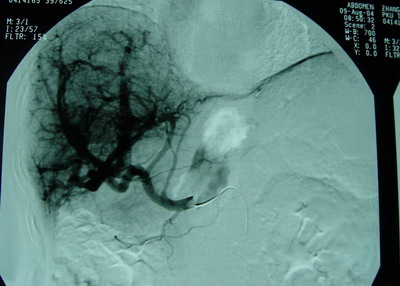

肝动脉、肠系膜上动脉、脾动脉造影见肝总动脉明显增粗,动脉期肝动脉及其分支显影良好,动脉早期可见门静脉显影,呈明显肝动脉—门静脉双轨征。肝实质期未见肿瘤染色。肠系膜上动脉间接门静脉显影,门静脉主干显影。门静脉血流方向为双向。可见胃底曲张血管逆行显影。